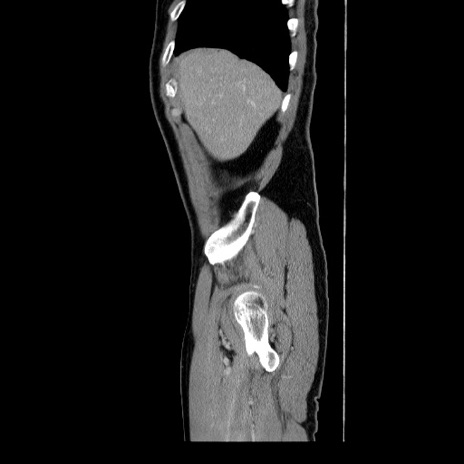

症例34(矢状断像)

【症例】60歳代 男性

【主訴】右鼠径部膨隆

【現病歴】1年程前より右鼠径部膨隆あり。自己にて還納可能だったため放置していた。3時間前より右鼠径部の脱出を認め、還納困難となり受診。

【身体所見】右鼠径部に小児頭大の膨隆あり。弾性硬であり、用手還納は困難。左鼠径部にも膨隆を認める。脱出はなし。

【データ】WBC 15500、CRP 測定なし